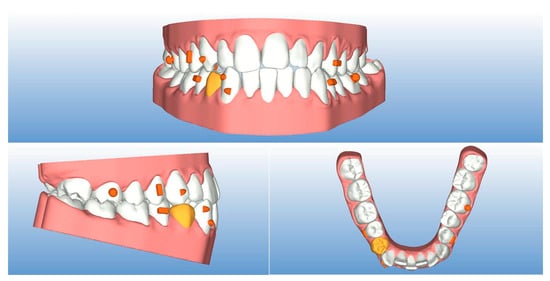

2. Case Report